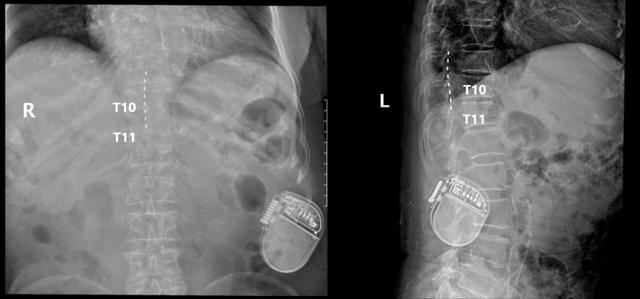

▲术后复查可见电极放置在T9-T11节段脊髓后方/图源 重医附二院疼痛科